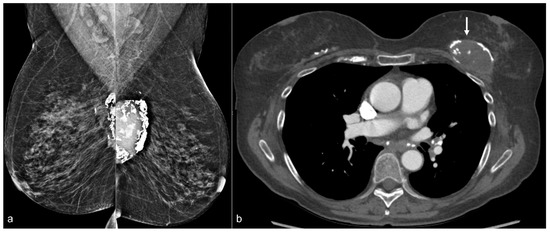

In some cases, it is possible to see a residual implant capsule (Figure 11). The capsule may calcify in the expected prepectoral location (Figure 12).

Figure 12. A 70-year-old patient’s mammogram (a) demonstrates bilateral calcified implant capsules with a dense mass in the left prepectoral location on the MLO view. CT (b) confirms a left breast seroma (arrow) with fibrous capsular calcifications.